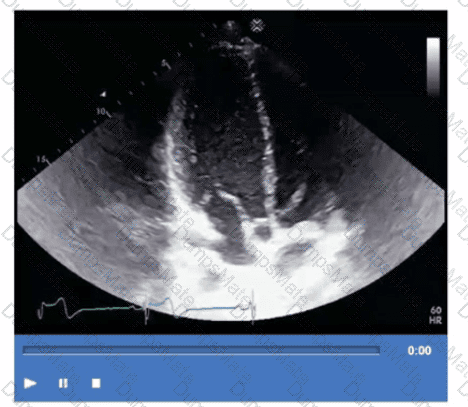

Questions 30

Which adjustment should be made to optimize this video?

AE-Adult-Echocardiography Question 30

Options:

A.

Increase compression

B.

Decrease overall gain

C.

Increase time gain compensation in the near field

D.

Decrease time gain compensation in the far field